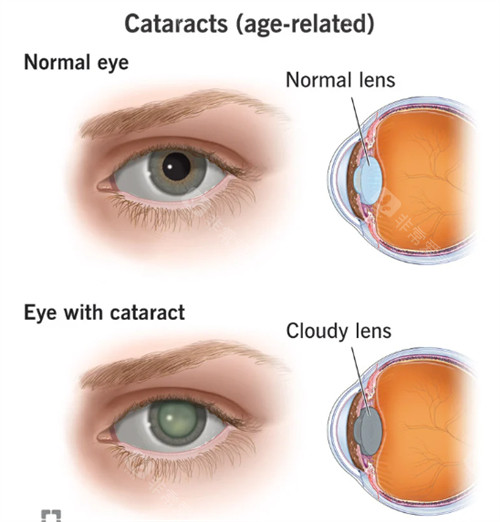

白内障正规开展了多种白内障手术,包括超声乳化白内障吸除术等,手术技术成熟,术后结果良好。